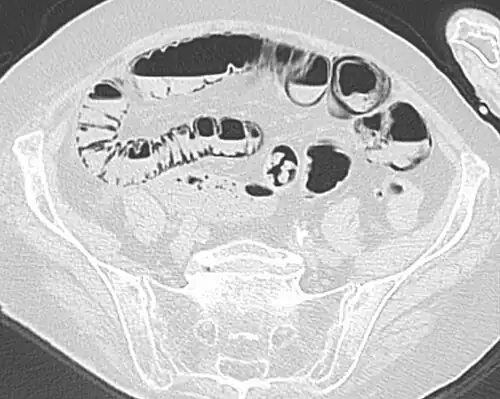

Pneumatosis intestinalis in computed tomography with intestinal ischemia. Lung window for better representation of the gas deposits in the intestinal walls. -